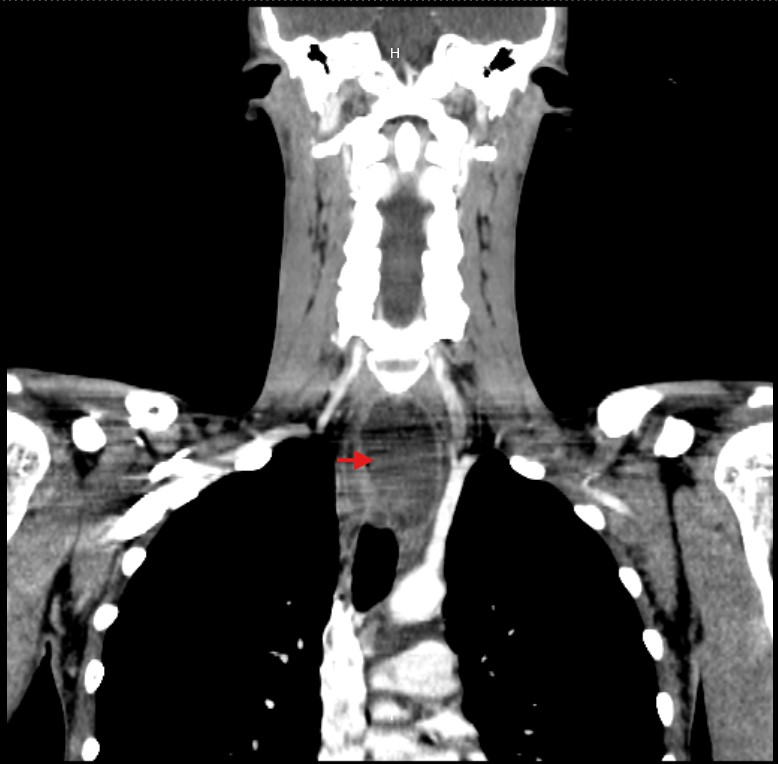

Due to the unclear etiology of the symptoms, combined with unremarkable initial studies and the subsequent development of dyspnea, a CT scan of the neck and thorax was performed. This revealed a large collection centered in the mediastinum, dissecting tissue planes and extending below the carina, reaching into the neck up to the left thyroid lobe. Gas was observed both within the collection and around the thyroid gland and mediastinum, with the esophagus displaced to the right by the mass effect of the abscess (Figure 1-5).

Figure 4 CT: Coronal view showing cervicomediastinal abscess.

Figure 5 CT: Coronal view showing mediastinal abscess at the level of the bronchial bifurcation.